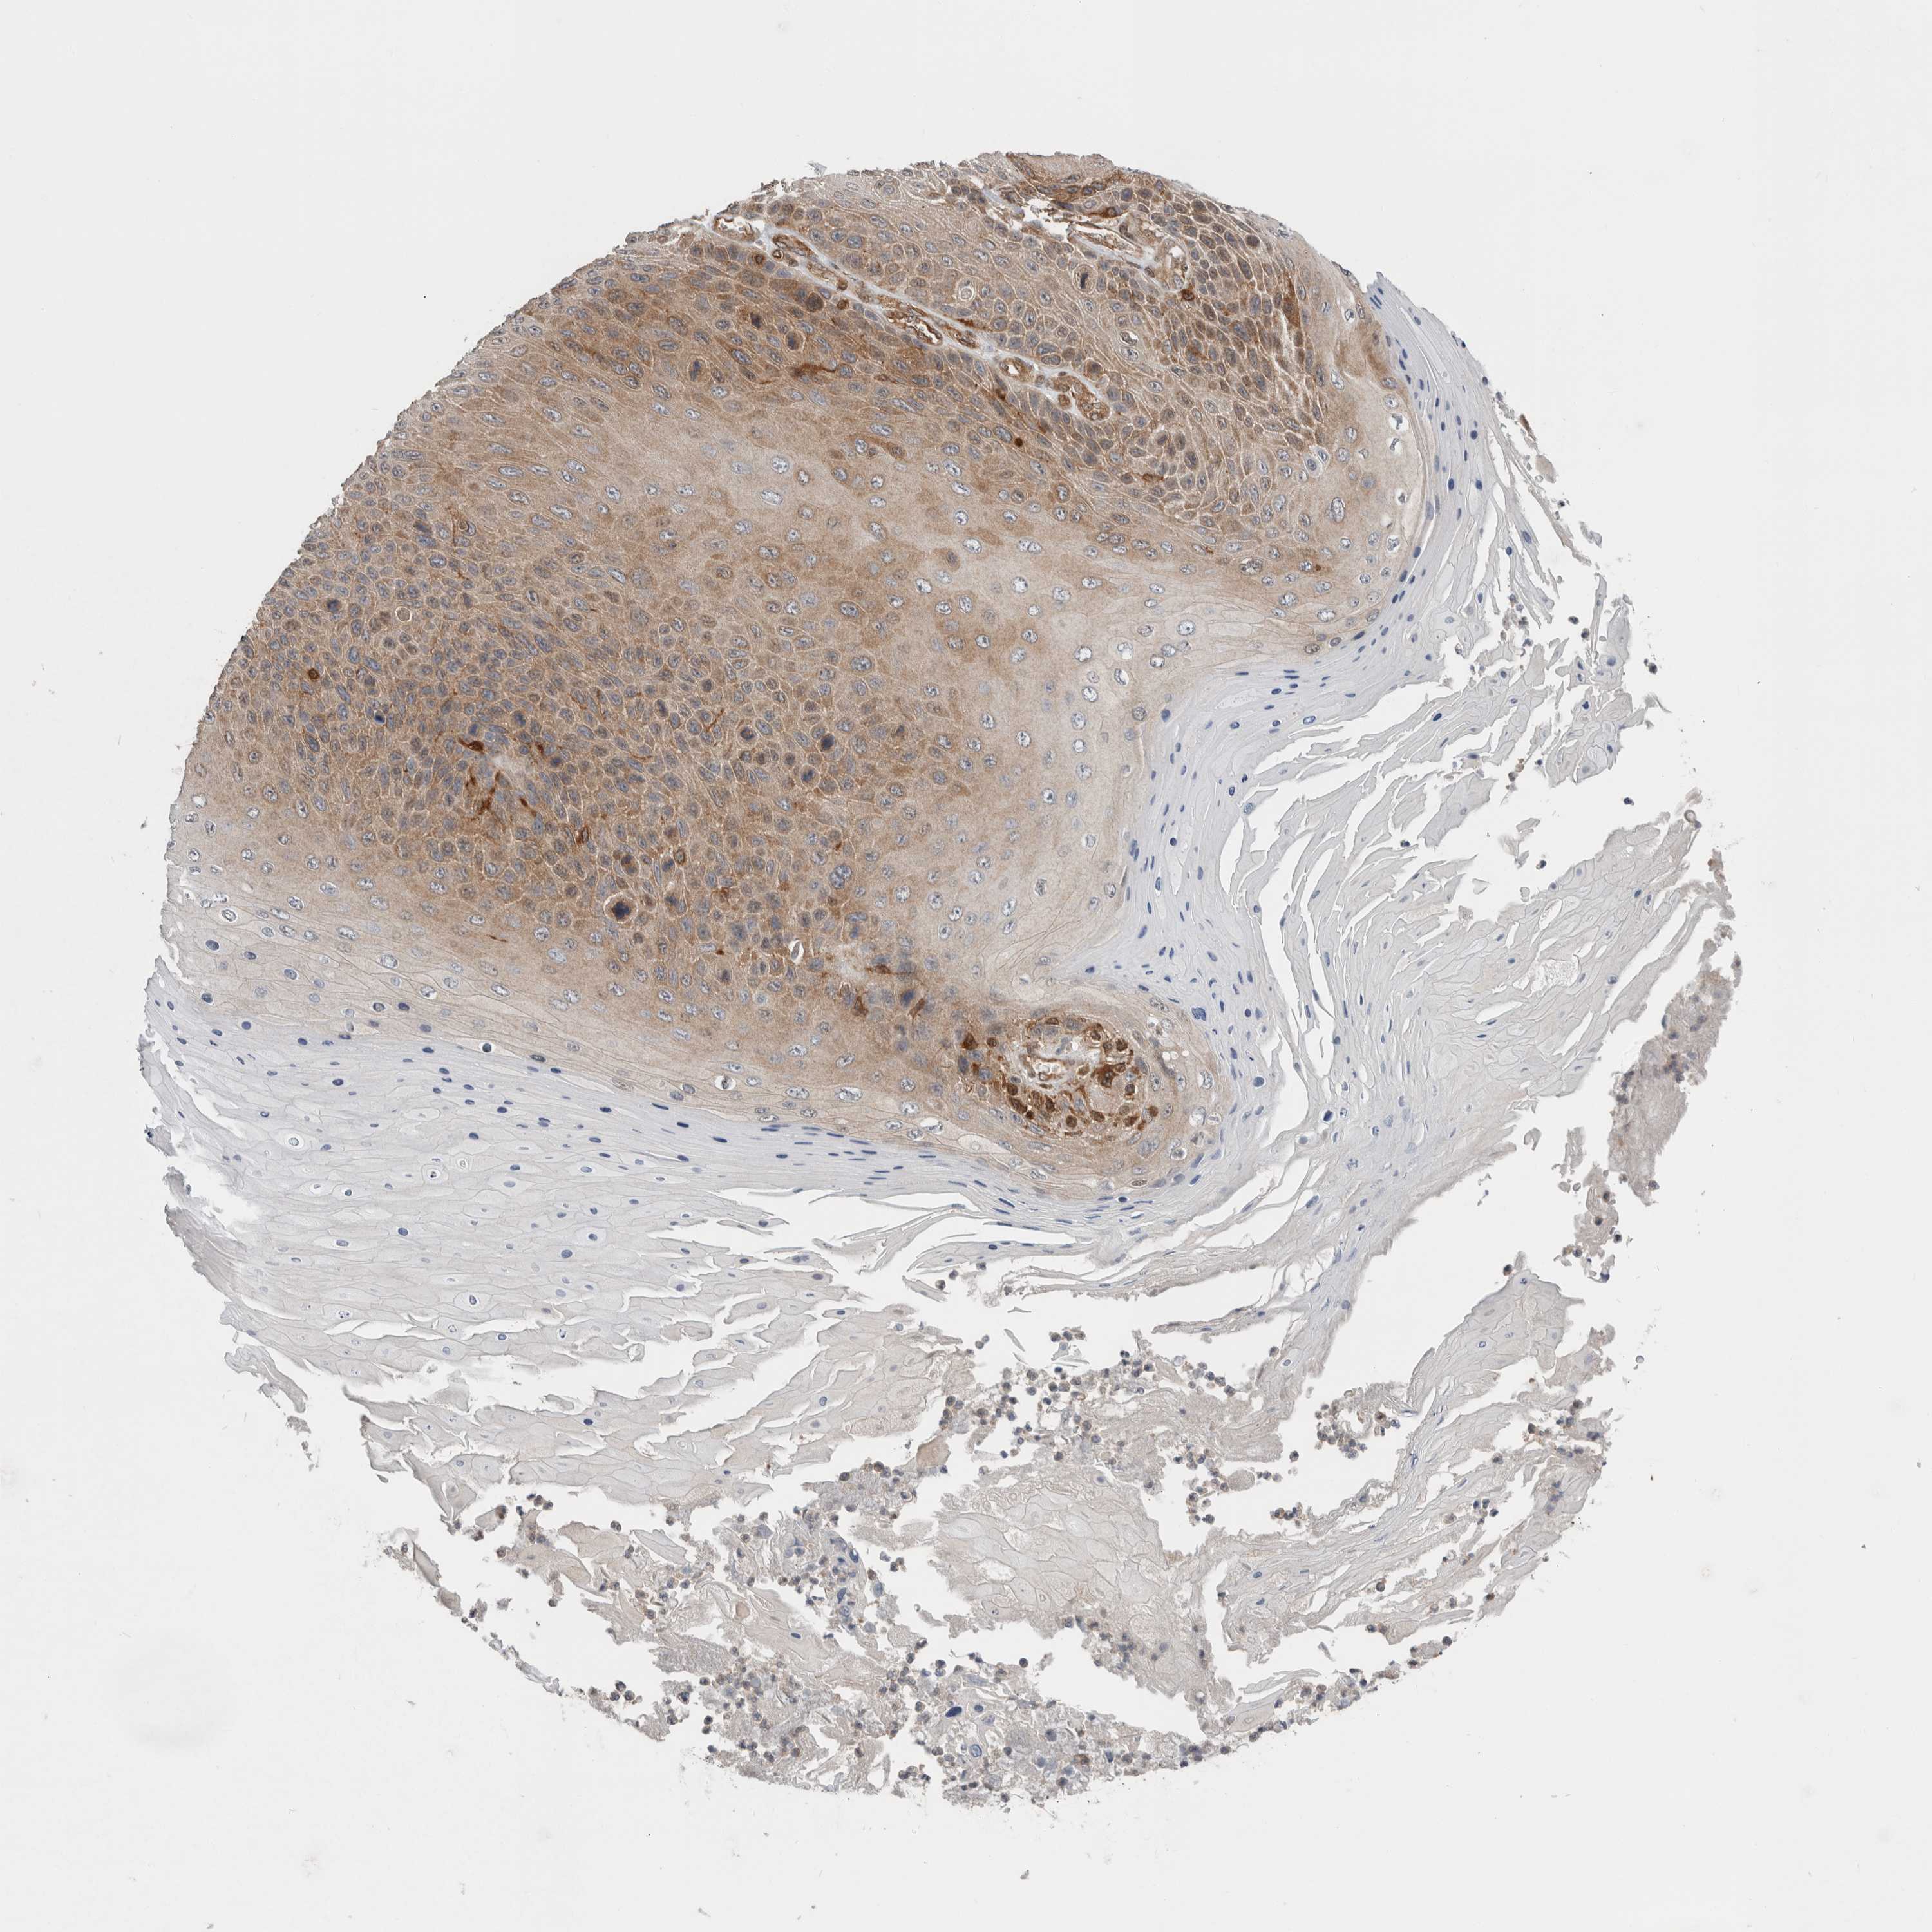

CANCER SKIN CANCER Show tissue menu

Basal cell and squamous cell cancer

SKIN CANCER - Protein expressioni

A mouse-over function shows sample information and annotation data. Click on an image to view it in a full screen mode. Samples can be filtered based on level of antibody staining by selecting one or several of the following categories: high, medium, low and not detected. The assay and annotation is described here.

Each image is clickable and will lead to virtual microscopy that enables deeper exploration of all samples and also displays staining intensity scores, fraction scores and subcellular localization as well as patient and tissue information for each sample.

HPA030419

HPA030420

HPA030422

CAB025196

CAB080286

CAB080287

Basal cell carcinoma

Squamous cell carcinoma, NOS

Squamous cell carcinoma, metastatic, NOS